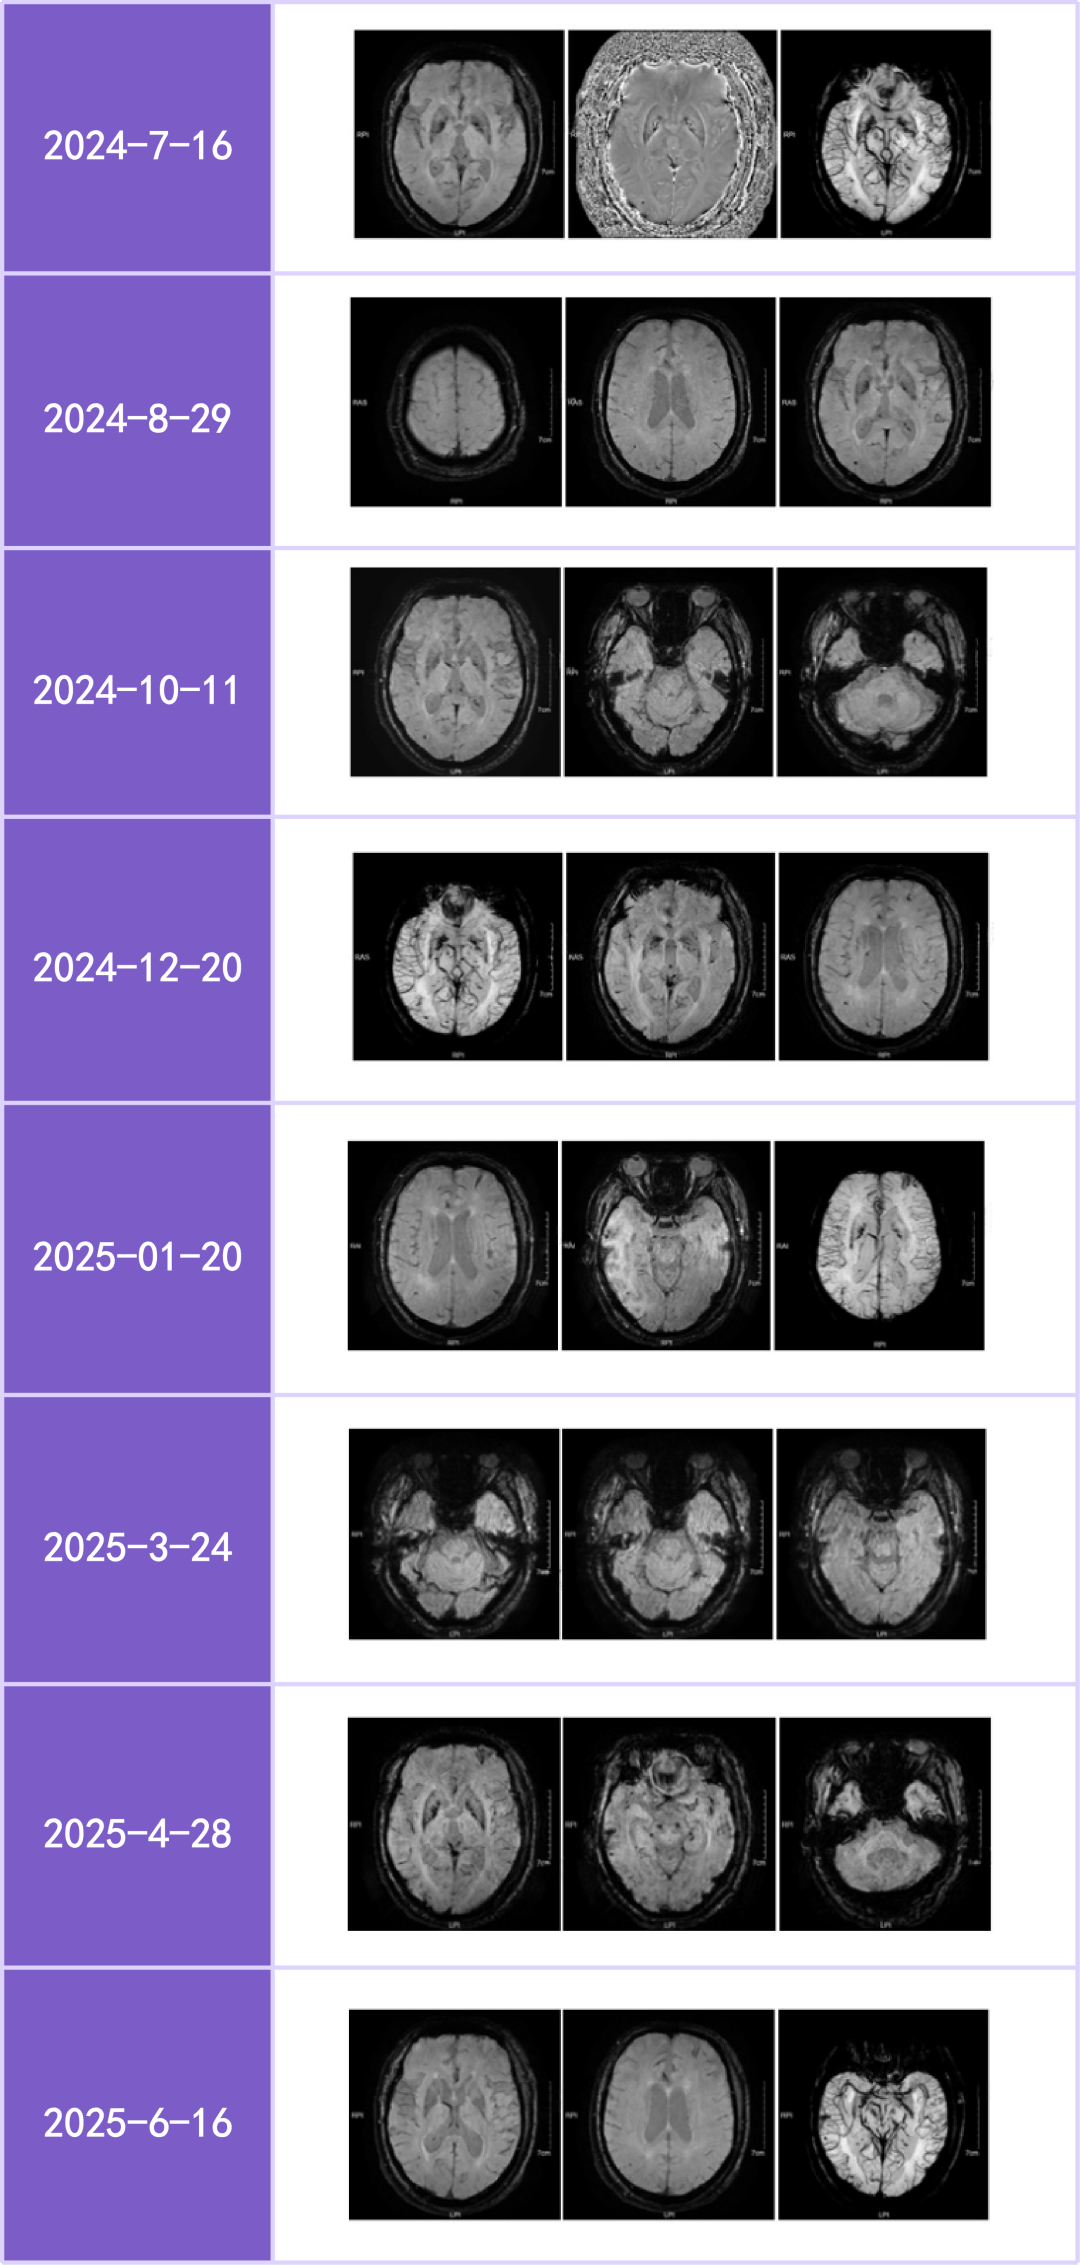

人民财讯3月2日电,热景生物(688068)3月2日公告,公司参股公司智源生物的全资子公司智源鸿晟自主研制的创新药AA001单抗Ib期临床研究完成首例阿尔茨海默病受试者入组给药。

AA001是一款由智源生物刘瑞田教授研发团队研制的单克隆抗体药物,适用于阿尔茨海默病源性轻度认知障碍及轻中度阿尔茨海默病患者的治疗。